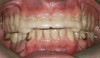

Initial examination revealed a partial edentulous patient with extensive wear of the maxillary anterior teeth and moderate wear in the mandibular teeth (Figure 1, Figure 2, Figure 3 , Figure 4, Figure 5, Figure 6 and Figure 7). The patient's maxillary and mandibular RPDs also showed excessive wear and multiple signs of fractures (Figure 2 and Figure 3). The patient had been wearing a mandibular nightguard for 8 years.

Figure 1  Intraoral anterior view of the patient presenting a severely worn maxillary dentition and loss of OVD.

Figure 1